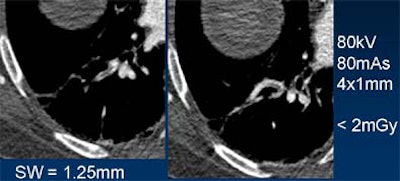

Even with minimal radiation dose, diagnostic images can be obtained by acquiring a near-isotropic secondary dataset and reconstructing with thicker slices in any plane.

| Reconstructing thicker sections (at right) reduces noise in low-dose, thin-collimation image acquisition. Images courtesy of Dr. Mathias Prokop. |